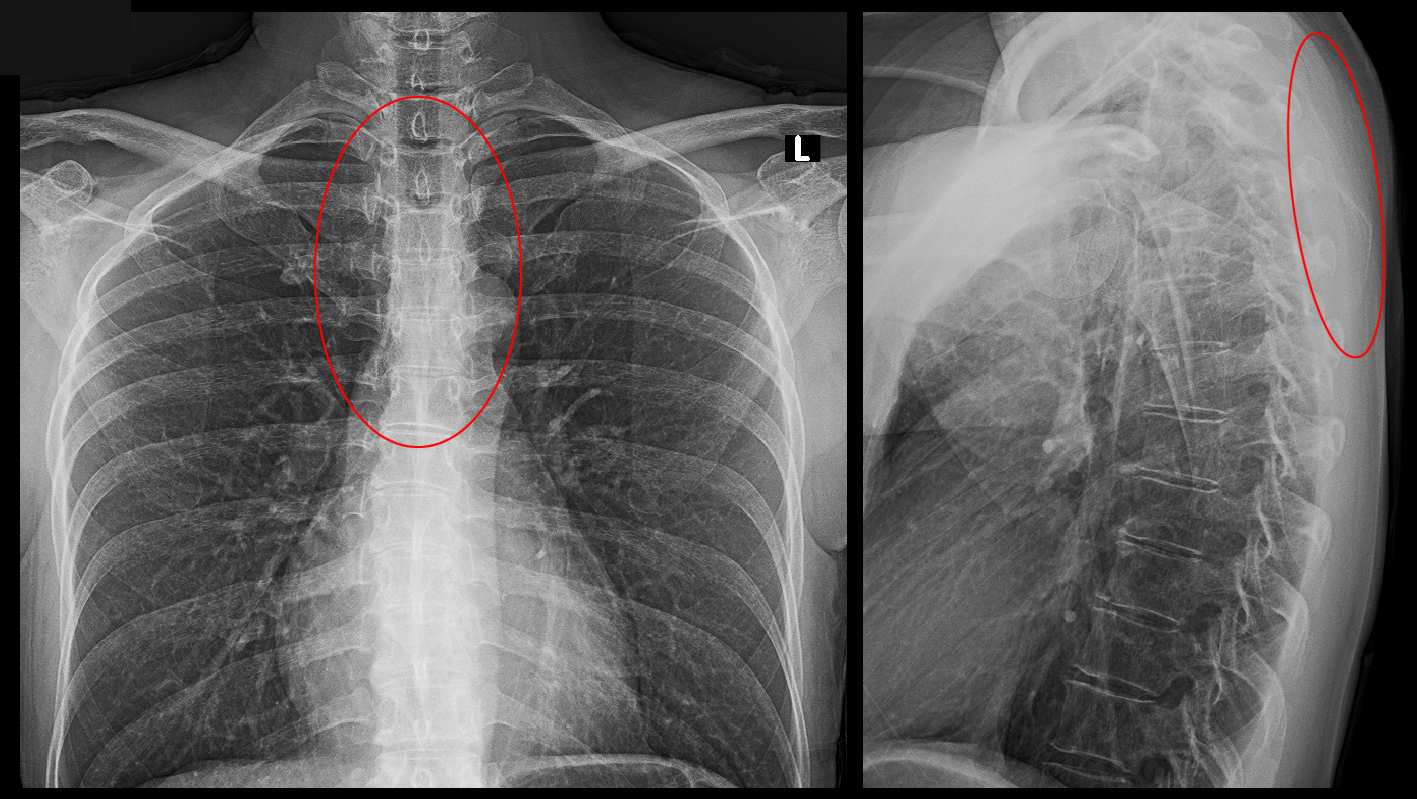

患者さんは「痛いんじゃなくて、苦しいんです。」と訴えていて、赤丸領域に苦しさを感じておられました。

XpDW.jpg

背中上部の症状は頚椎に起因することも多いので、頚椎のレントゲン像もチェックしています。